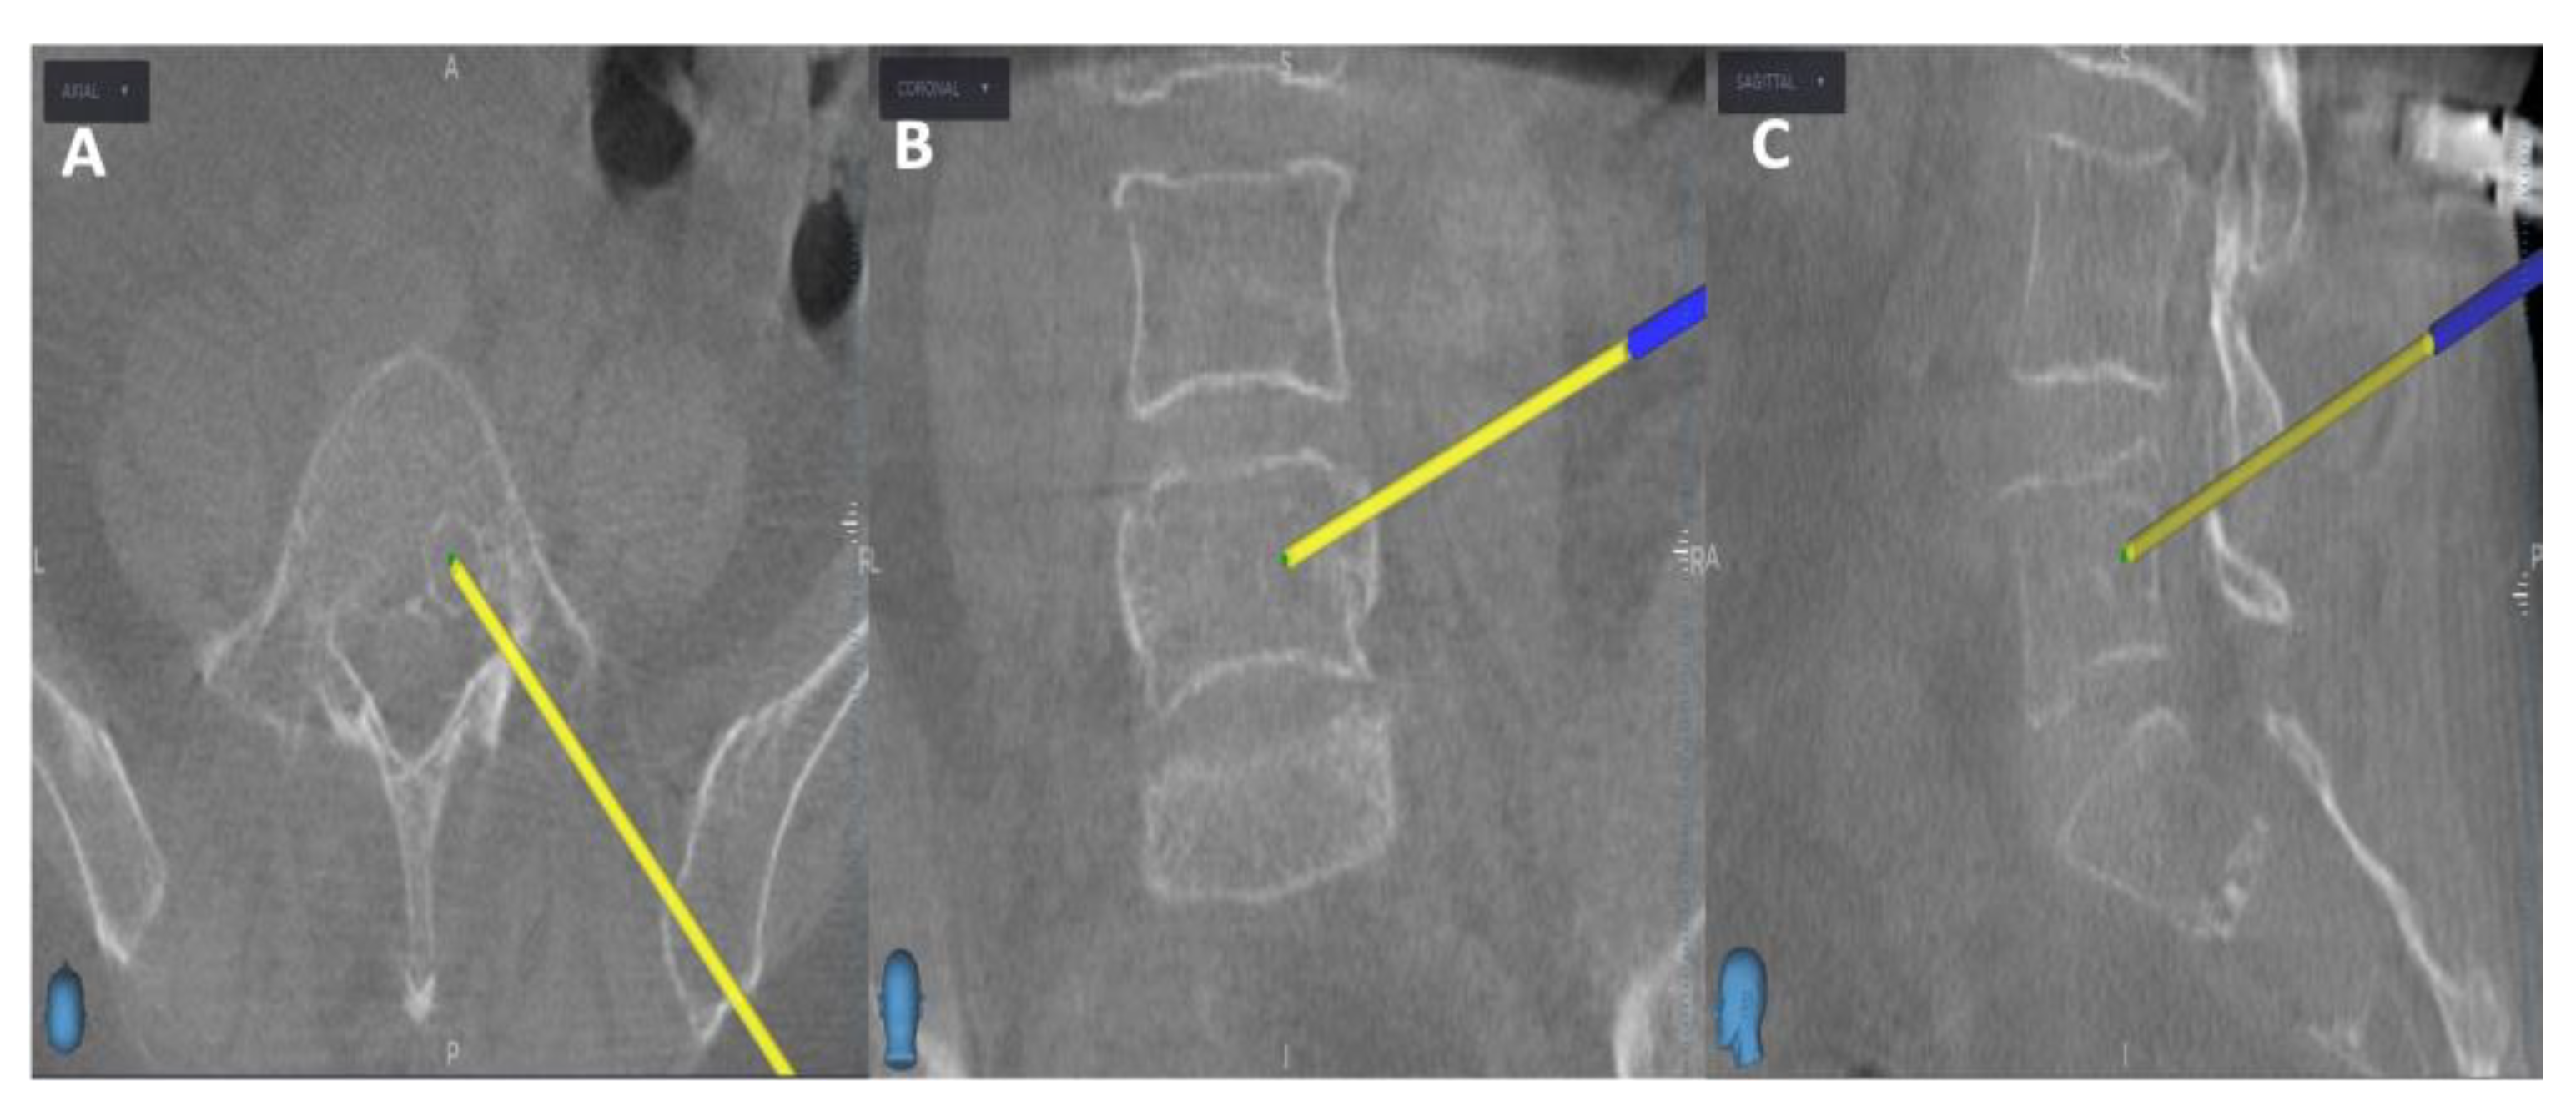

Initially, the entry point is determined through the O-arm scan (Figure 1). Next, the target point for sampling is set using an MRI scan (Figure 2). Afterward, the surgical plan for the needle biopsy is progressed by utilizing the instrument projection function.

Figure 1. Intraoperative O-arm scan, the yellow projection line indicates the entry point for the needle biopsy, with A) Axial view, B) Coronal view, and C) Sagittal view.